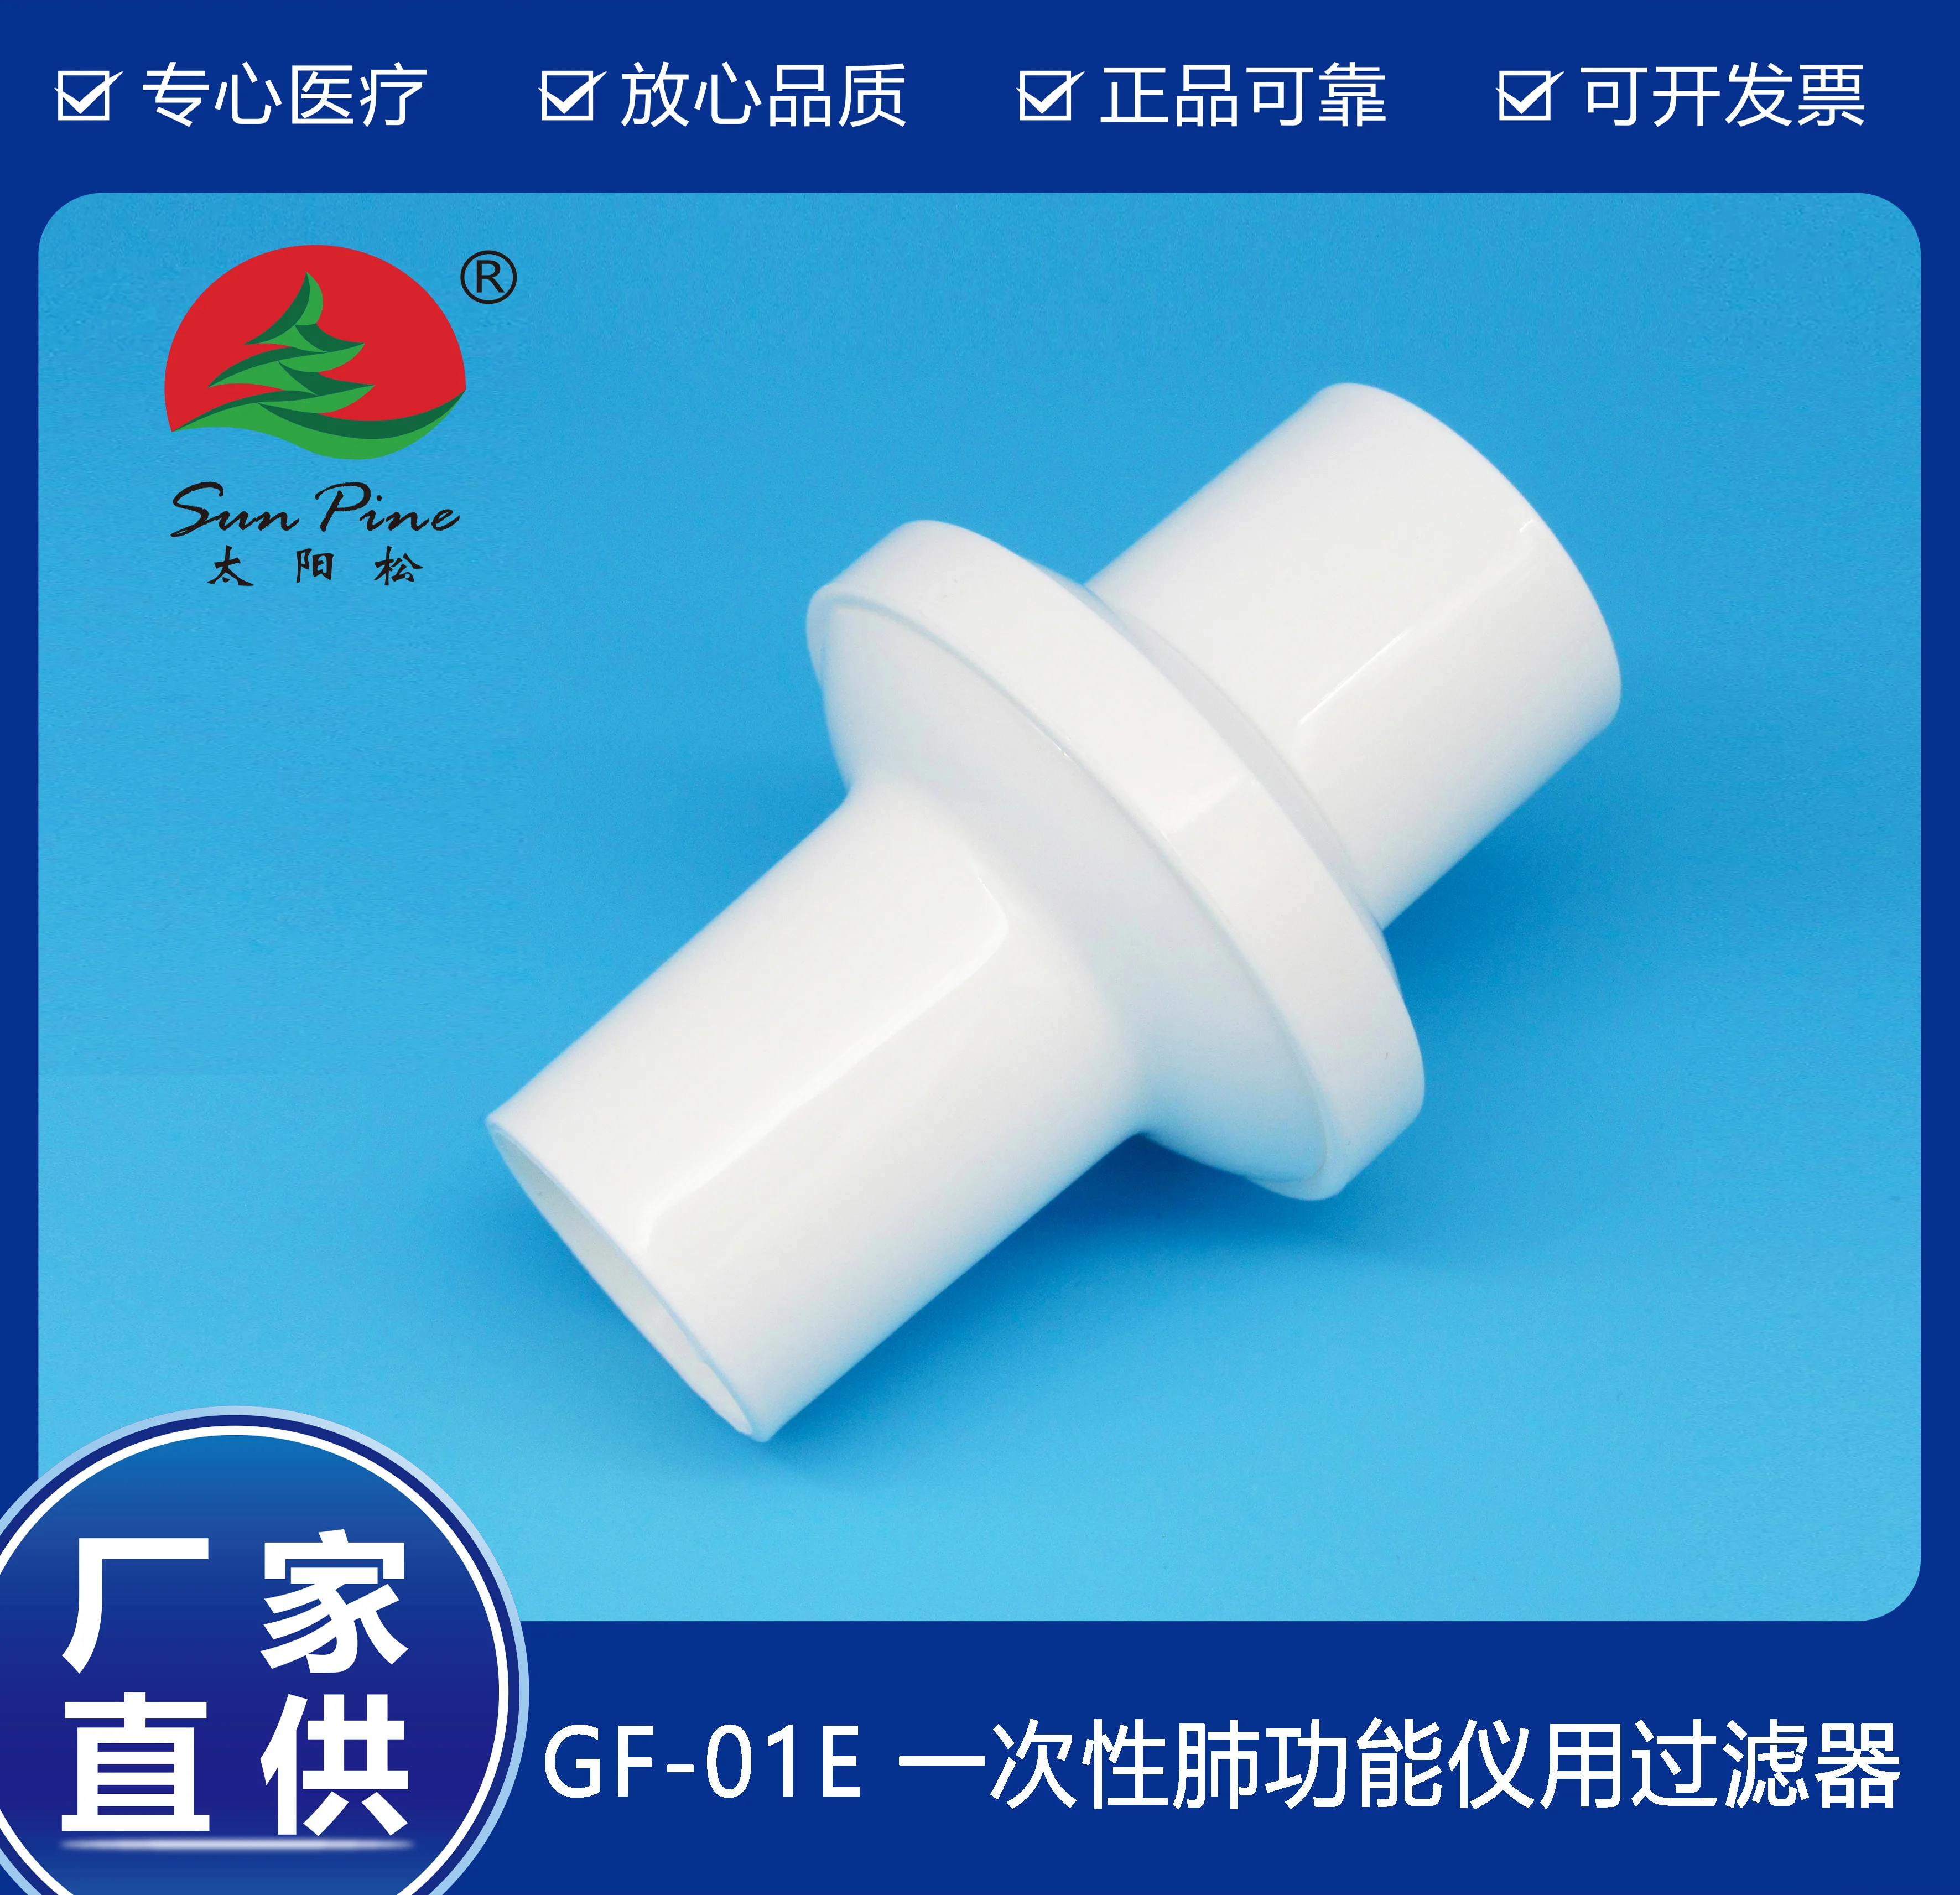

中山高榮電子科技有限公司是一家集自主研制,生產(chǎn)和銷(xiāo)售一體的高新技術(shù)醫(yī)療器械生產(chǎn)企業(yè),嚴(yán)格按照CFDA認(rèn)證,遵守國(guó)家醫(yī)療器械法規(guī)建立了完善的質(zhì)量管理體系,確保提供給客戶(hù)的醫(yī)療器械產(chǎn)品安全健康。公司擁有十萬(wàn)級(jí)、萬(wàn)級(jí)潔凈生產(chǎn)車(chē)間,環(huán)氧乙烷滅菌車(chē)間,有專(zhuān)門(mén)的物理實(shí)驗(yàn)室、理化實(shí)驗(yàn)室和微生物實(shí)驗(yàn)室以及醫(yī)電研發(fā)室、醫(yī)電生產(chǎn)車(chē)間。主要產(chǎn)品有:“太陽(yáng)松”品牌:一次性使用呼吸過(guò)濾器,一次性肺功能儀用過(guò)濾器,咬嘴;“凱華”品牌:醫(yī)用電子產(chǎn)品,肺功能檢查儀等,其中過(guò)濾器,咬嘴可匹配市場(chǎng)上各種不同品牌型號(hào)的肺功能儀使用,可以降低患者吸入或呼出顆粒性物質(zhì)的數(shù)量,防止污染儀器,大限度保障每位受測(cè)者健康安全.